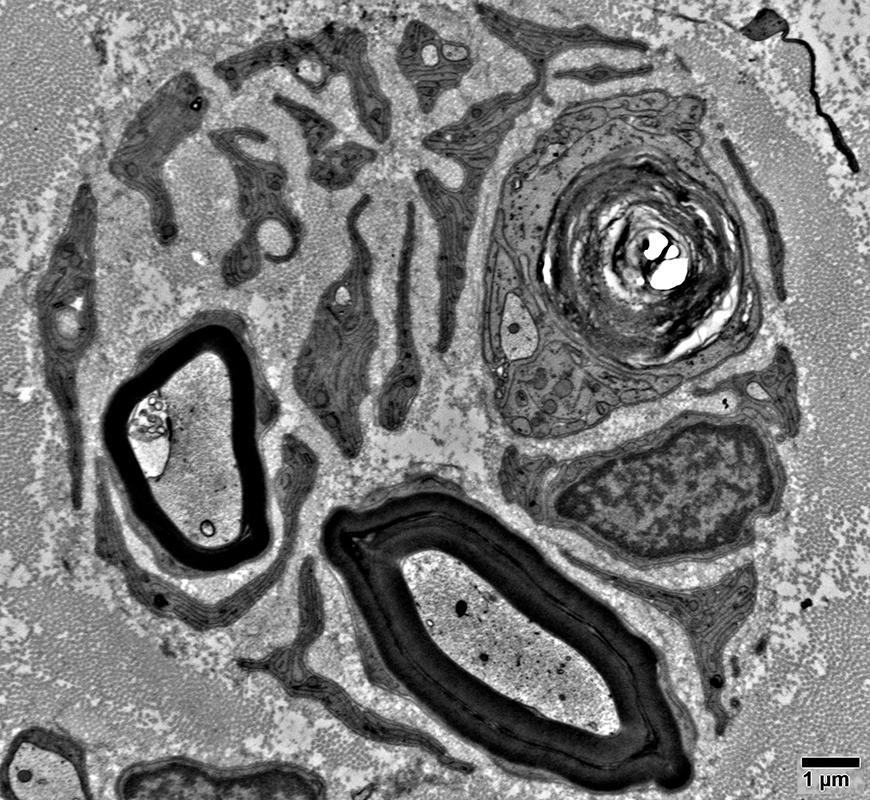

Collagen Pockets

Schwann cell processes may surround collagen

Büngner Bands

Interdigitated Schwann cell processes

Collagen Bulbs

Collagen bulb

No associated axon

Mostly composed of collagen

Surrounded by fibroblast processes

Contains normal & large Schwann cell proceses